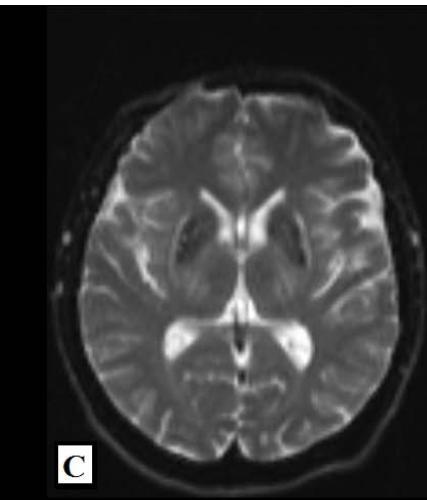

We report a rare case of Wilson’s Disease with neurologic features in a 31-year-old man. This disease consists of a disturbance of copper metabolism secondary to a mutation in the gene responsible for encoding the tissue transporter and the enzyme that incorporates the excess element into bile, generating toxic accumulation in the liver, cornea, and central nervous system. According to his wife, the patient had been treated for an unspecified mood disorder. The clinical picture was characterized by depressive mood, anhedonia, and anxiety. He had his first seizure episode on December 3rd, 2021. He progressed with dysarthria, ataxic gait, dystonia of the right-hand flexor muscles, and intermittent urinary incontinence. Marked worsening was observed after the diagnosis of COVID-19 in February 2022. At the clinical evaluation on March 24th, risorius muscle dystonia (risus sardonicus), resting tremor, and Kayser Fleischer rings at slit-lamp examination was also noted.

Detailed image from a research journal sample.